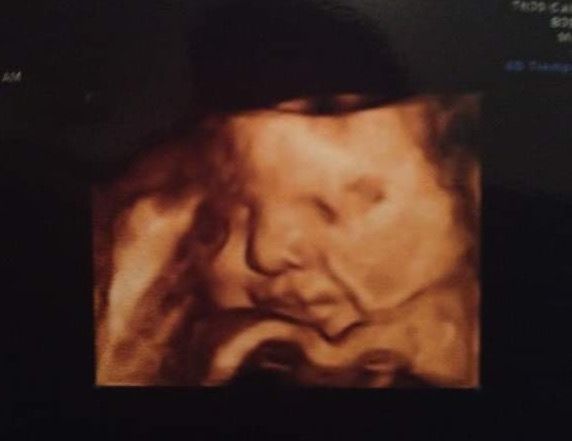

Recomiendo ampliamente a la doctora por la excelente atención que recibí. Desde el inicio fue muy amable, dedicada y profesional, lo que me hizo sentir tranquila y en confianza en todo momento. Durante la ecografía me fue explicando con paciencia cada parte del cuerpo de mi bebé, resolviendo todas mis dudas y haciendo de la experiencia algo muy especial. Me encantó poder verlo bien y sentir que estaba en buenas manos. Sin duda, una atención de calidad que se agradece muchísimo.

• Dra. Issumi A. Meza Meneses • Ultrasonido estructural del segundo trimestre •